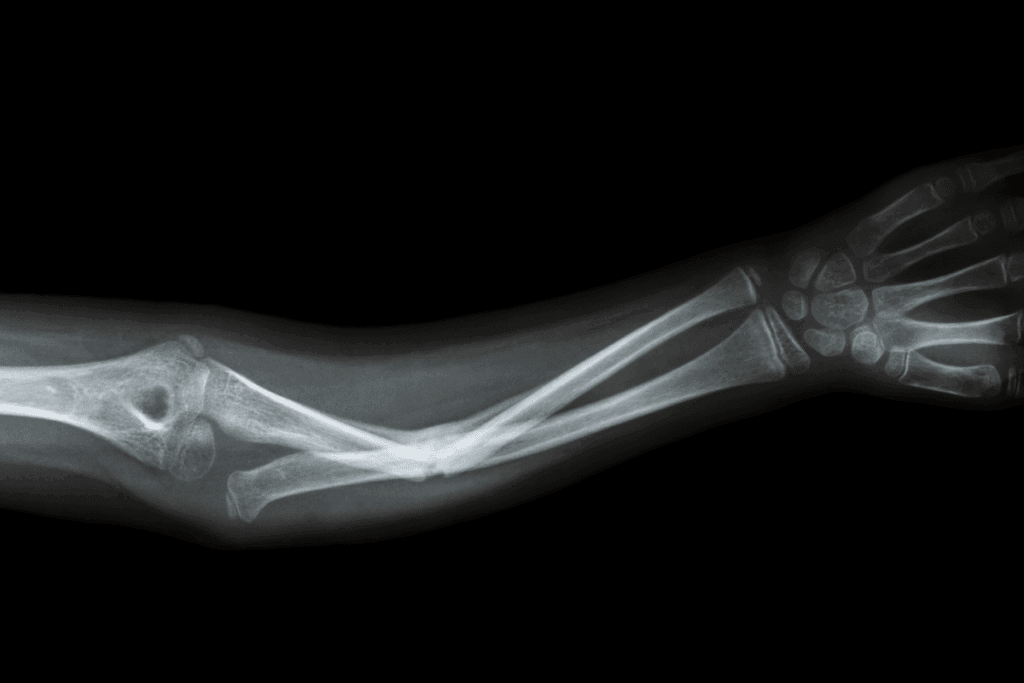

Identifying Fracture Problems in Different Body Parts

Upper Extremity Fracture Complications

Fractures in the arms, wrists, and hands can cause specific issues. These might include:

- Reduced mobility and strength in the affected arm or hand

- Nerve damage leading to numbness or tingling

- Impaired function of the wrist or elbow

Common complications of upper extremity fractures include malunion, where the bone heals in an incorrect position, and nonunion, where the bone fails to heal properly.